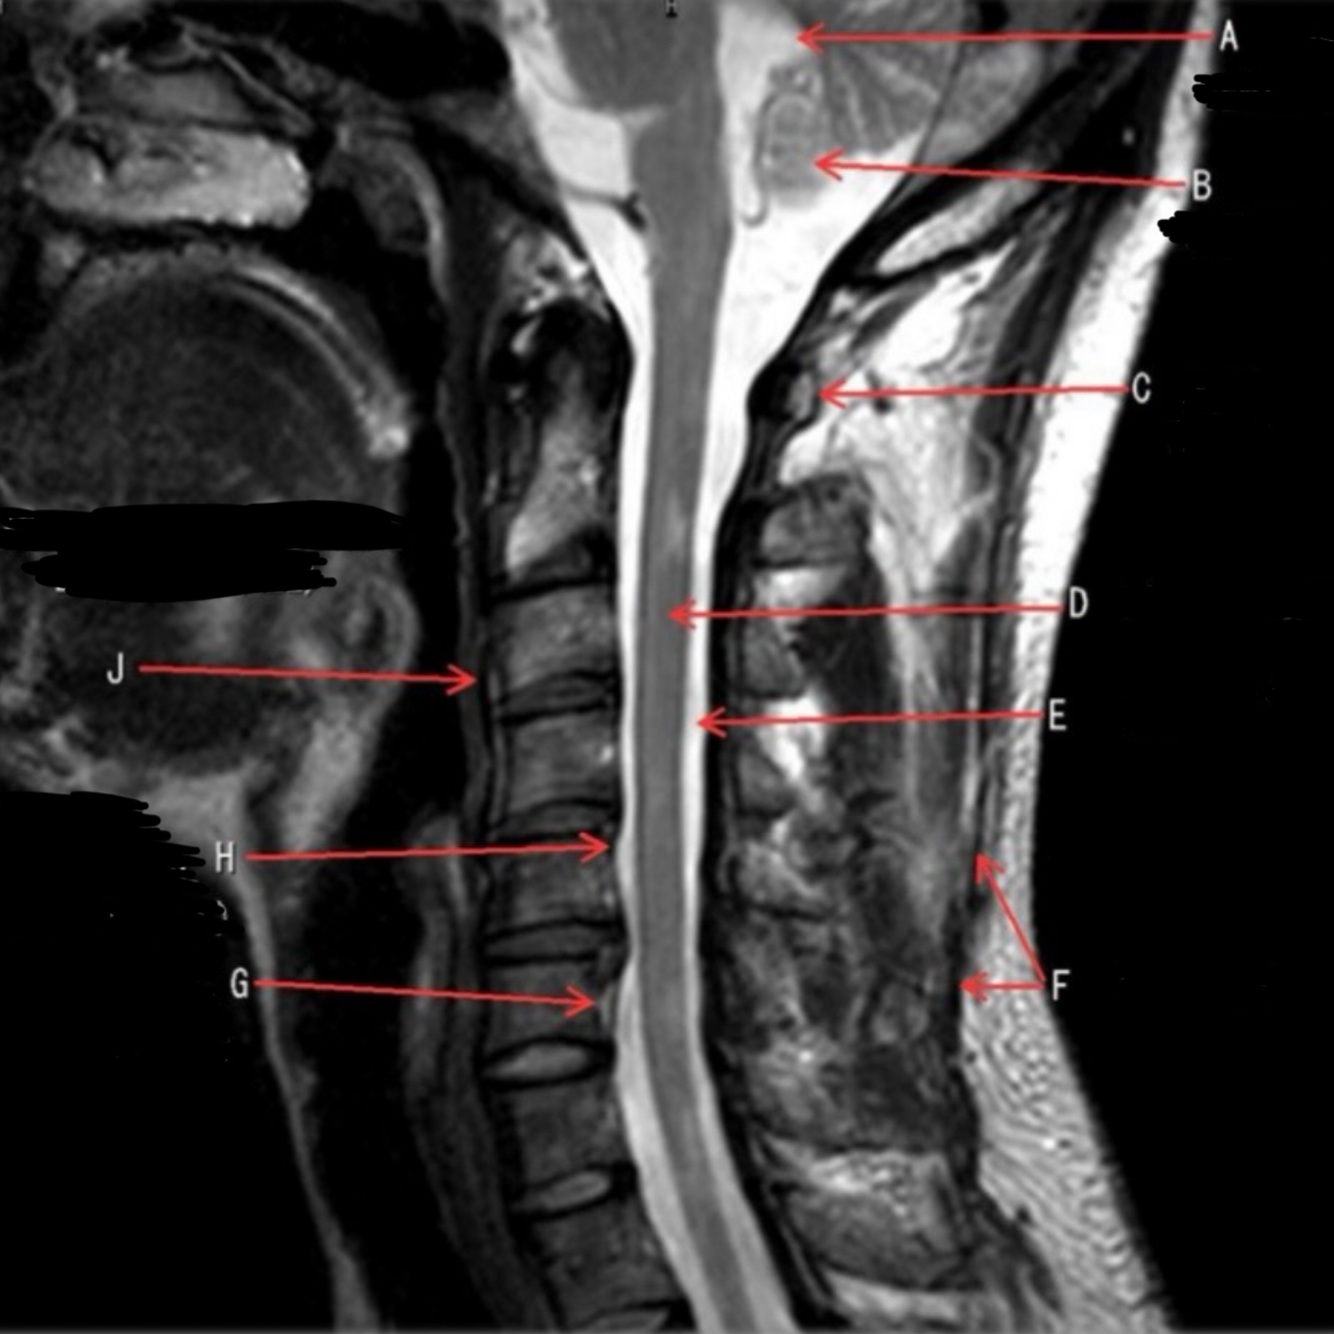

55

CEREBELLUM

56

What is letter B?

SPINAL CORD

57

What is letter C?

CSF

58

What is letter D?

SPINOUS PROCESS

59

What is letter E?

S1 VERTEBRAL BODY

60

What is letter F?

INTERVERTEBRAL DISK SPACE

61

What is letter G?

12TH THORACIC VERTEBRAE

62

What is letter H?

7TH THORACIC VERTEBRAE

63

What is letter J?

SUPRASTERNAL NOTCH

64

What is letter K?

3RD CERVICAL VERTEBRAE

65

What is letter L?

PONS